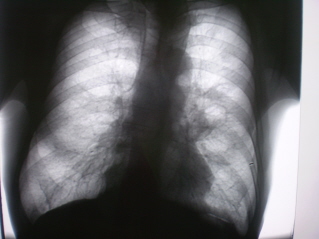

В 2007 году, находясь на стационарном лечении в терапевтическом отделении по поводу хронического бронхита, пневмосклероза был направлен на флюорографическое исследование органов грудной полости. На обзорной цифровой флюорограмме органов грудной полости, произведенной в прямой стандартной проекции с обеих сторон в базальных, преимущественно в медио – базальных отделах определяется усиление, обогащение и деформация легочного рисунка за счет явлений хронического бронхита и пневмосклероза. Имеет место некоторая деформация грудной клетки, сужение межреберных промежутков слева в верхних отделах. В грудном отделе позвоночника выраженные явления дистрофического характера в виде явлений межпозвонкового остеохондроза и деформирующего спондилеза. Определяется некоторое расширение тени левого корня, преимущественно в области тела, с некоторой гомогенизацией и потерей четкости наружного контура корня. В прикорневой области усиление и обогащение рисунка, преимущественно за счет линейных компонентов, направленных к периферии.

На иллюстрациях 1 и 2 – картина флюорографического изображения, с последующей оцифровкой изображения с применением эквилизации и увеличения. После исследования заподозрен рак левого лёгкого, с преимущественным «перибронхиальным ростом». Согласно «стандарту» произведено рентгенологическое дообследование пациента – прямая и левая боковая рентгенограммы; линейные томограммы в прямой проекции через левый – срезы 9, 10 11 см. После проведенного исследования был выставлен диагноз «Рак левого лёгкого, исходящий из корня, с преимущественным перибронхиальным ростом». Пациент консультирован в онкологическом диспансере. Было проведено дообследование, рекомендовано проведение противовоспалительного лечения. После проведения указанного лечения, при повторной консультации в онкологическом диспансере (в том числе с проведением рентгенографии) отмечена положительная динамика и выставлен диагноз хронического неспецифического воспалительного процесса.